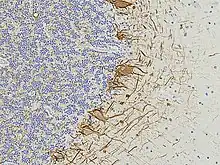

- Shaw G, Madorsky I, Li Y, Wang Y, Rana S, Jorgensen M, Fuller DD (April 2023). "Uman Type Neurofilament Light Antibodies Are Effective Reagents for the Imaging of Neurodegeneration". Brain Communications. 5 (2): fcad067. doi:10.1093/braincomms/fcad067. PMC 10120172. PMID 37091583.